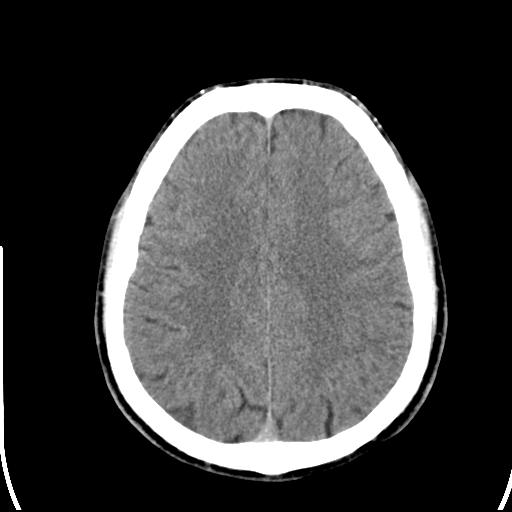

头皮下高密度结节影???临床上在老年男性比较常见。大家看看是什么?成因是? 本例患者,男性,51岁。外伤来诊。无染发史及发根植入史。

考虑异物。

皮下钙化点

没见过,可能为毛囊钙化。